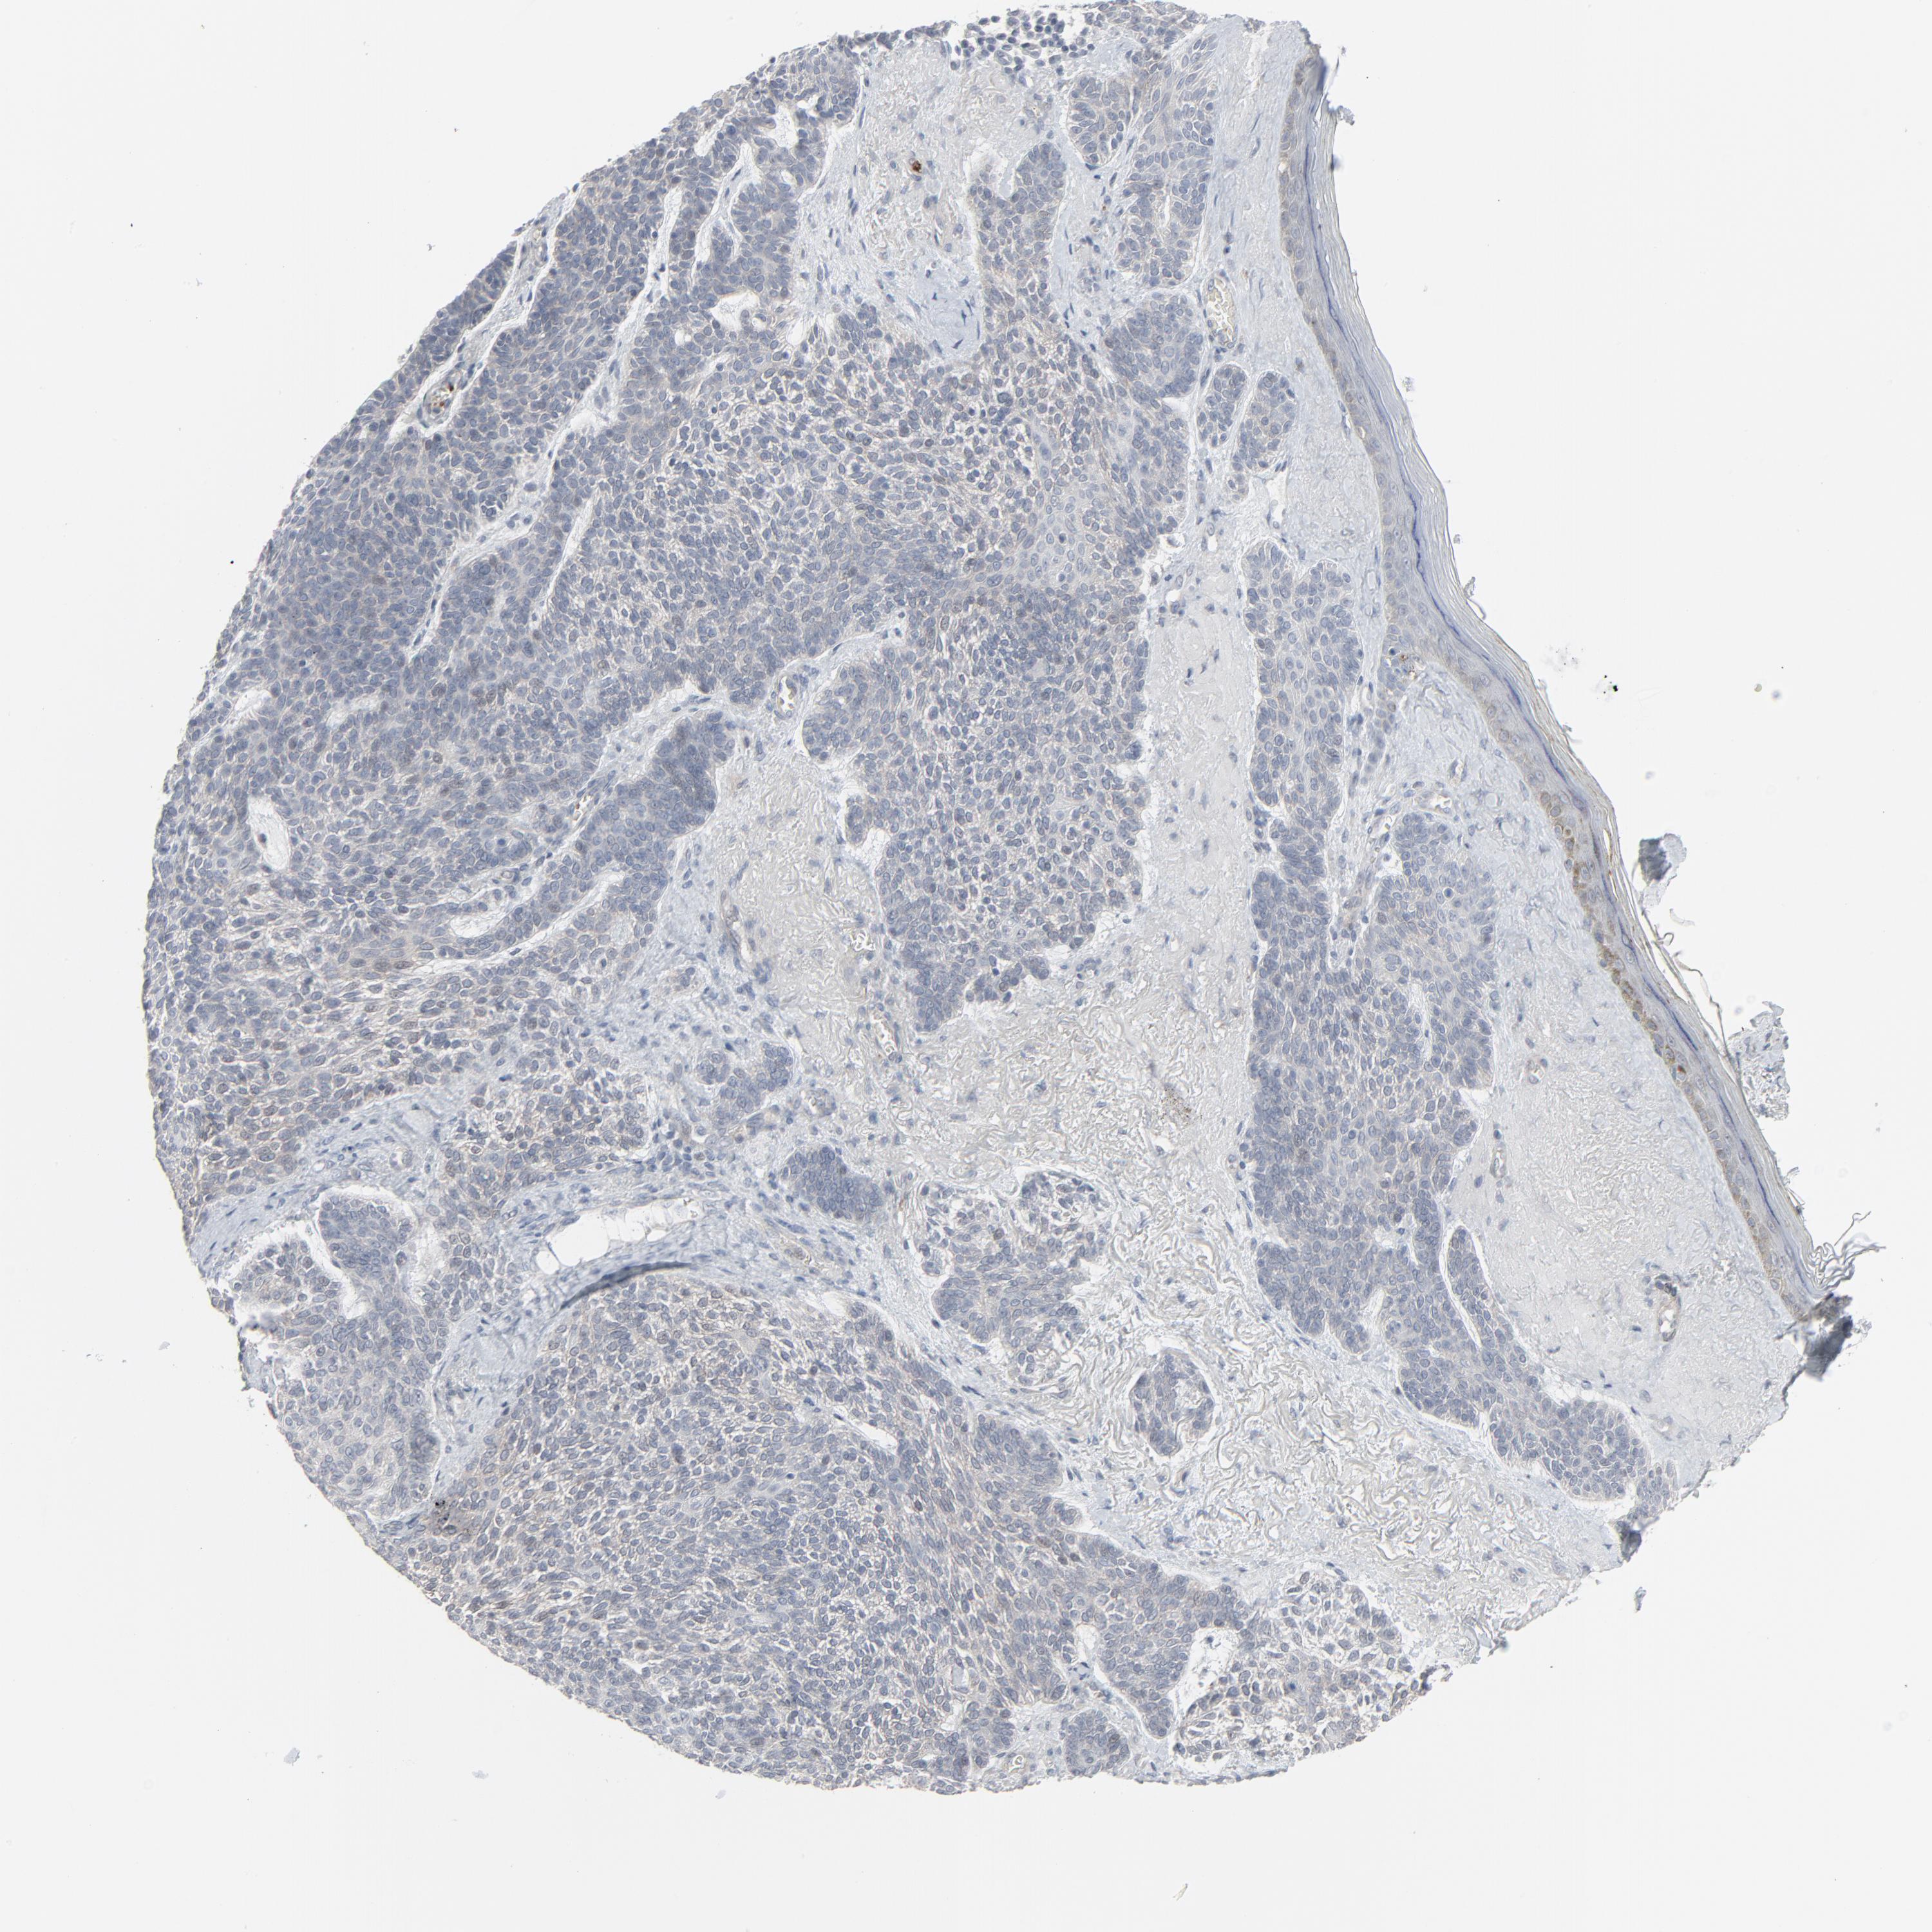

CANCER SKIN CANCER Show tissue menu

Basal cell and squamous cell cancer

SKIN CANCER - Protein expressioni

A mouse-over function shows sample information and annotation data. Click on an image to view it in a full screen mode. Samples can be filtered based on level of antibody staining by selecting one or several of the following categories: high, medium, low and not detected. The assay and annotation is described here.

Each image is clickable and will lead to virtual microscopy that enables deeper exploration of all samples and also displays staining intensity scores, fraction scores and subcellular localization as well as patient and tissue information for each sample.

Antibody HPA003278

Antibody CAB022450

Squamous cell carcinoma, NOS

Basal cell carcinoma